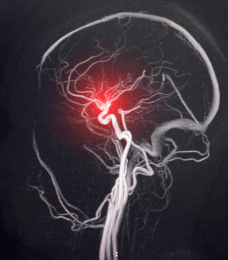

안녕하세요, 여러분! 혹시 모야모야병이라고 들어보신 적 있으세요? 이는 뇌동맥 조영 영상이 아지랑이처럼 흐물흐물해지면서 뿌연 담배 연기 모양과 비슷하다고 하여 "모야모야"라고 명명되었다고 하는데요. 이름이 참 재미있는 것 같습니다. 허나, 이 병은 아직 정확한 원인이 밝혀지지 않았으며, 주로 아이들에게 많이 발병하는 무서운 병 중 하나라고 합니다. 오늘은 모야모야병에 대한 증상, 원인, 진단 그리고 치료 및 예방법까지 자세히 알아보는 시간을 가져보도록 하겠습니다.

뇌혈관의 구조를 확인하기 위해 영상 검사가 주로 사용됩니다. 이러한 검사에는 자기 공명영상 촬영(MRI), 컴퓨터 단층 촬영(CT), 혈관조영술(angiography)이 포함될 수 있습니다. MRI 및 CT는 뇌혈관의 형태와 혈류를 시각화하는 데 사용됩니다. 혈관조영술은 혈관 내부에 감압제를 삽입하여 혈관의 형태와 혈류를 더 자세히 확인합니다.